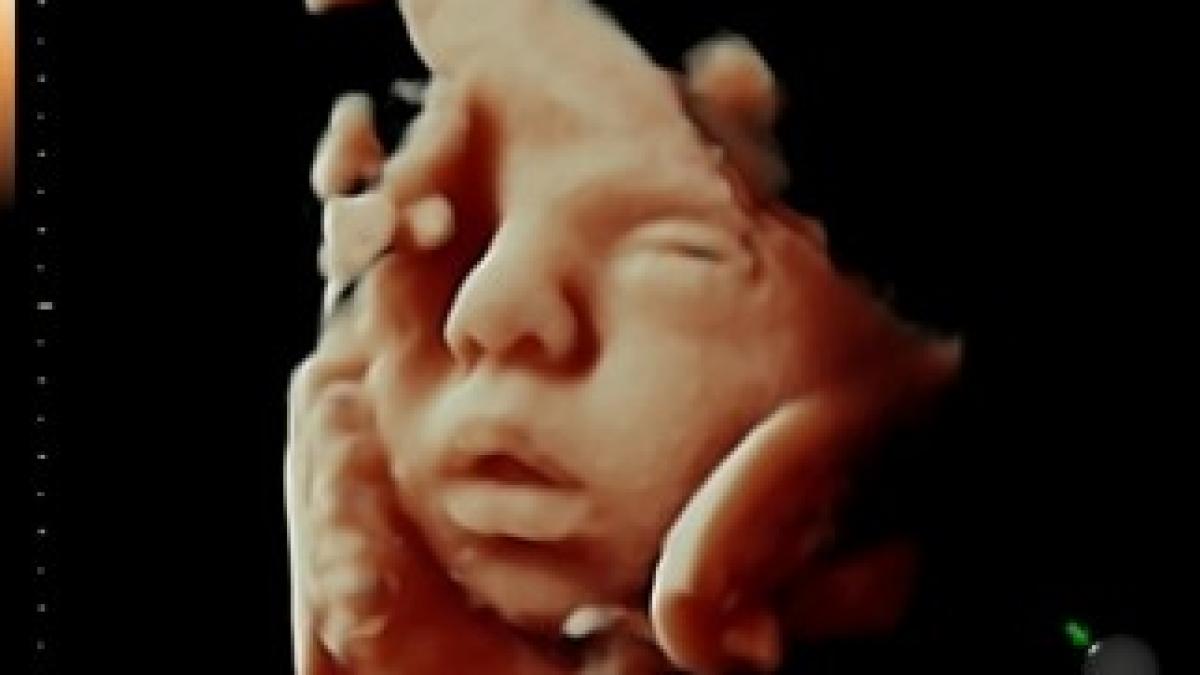

Noua modă în ecografia fetală: 3D și color

Graţie unei noi tehnologii, viitorii părinţi au şansa de a vedea fetusul din pântece color şi 3D, scrie Inovaţia tehnologică permite doctorilor să detecteze posibilele probleme cu care se confruntă fetusul mult mai repede decât era posibil până acum.

Un nou software foloseşte datele obţinute cu ajutorul unui scanner cu ultrasunete 3D şi adaugă culoare, textura pielii, lumini şi umbre pentru a oferi o imagine de o claritate excepţională, permiţând părinţilor să vadă faţa copilului nou născut înainte să se nască.

Tehnologia a fost concepută de doctorul Bernard Benoit de la Spitalul Prinţesa Grace din Monaco.Medicul este renumit în întreaga lume pentru inovaţiile pe care le-a adus în domeniul tehnologiilor cu ultrasunete.